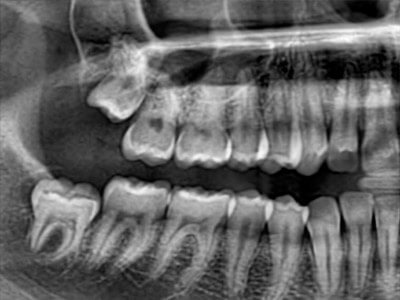

Pro Patient: Our state-of-the-art cone-beam computed tomography (CBCT) technology could selectively image the sinus, oral maxillofacial, para-nasal sinuses, ear & throat regions.

3D Imaging with Field of View sizes available in:

Proactive Dental Management thru our 3D Imaging Manipulation Software

With Oral Maxillofacial CT Scans, your dentist enhances his ability to proactively manage your health concern thru accurate diagnosis & better treatment planning. Moreover, the patient benefits from a painless,low radiation dose CT Scan procedure.